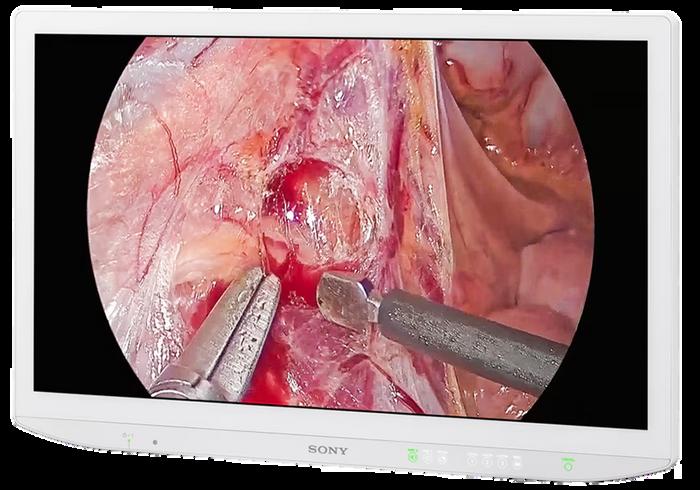

“One of the main challenges I’ve faced in my current role as an advanced engineer is maintaining a consistent preventive maintenance schedule in the cath labs. These labs are high-demand environments where patient care is always the top priority, so finding the right windows of time to perform thorough maintenance without disrupting critical procedures can be quite challenging,” Tinsley says.

He says that in addition to these challenges, he has been involved in projects focused on upgrading and optimizing the imaging systems within the cath, IR, OR, and EP labs.

“These projects have included system updates, integration of new technologies, and workflow improvements aimed at improving operational reliability and supporting the clinical teams in delivering quality care,” Tinsley says.